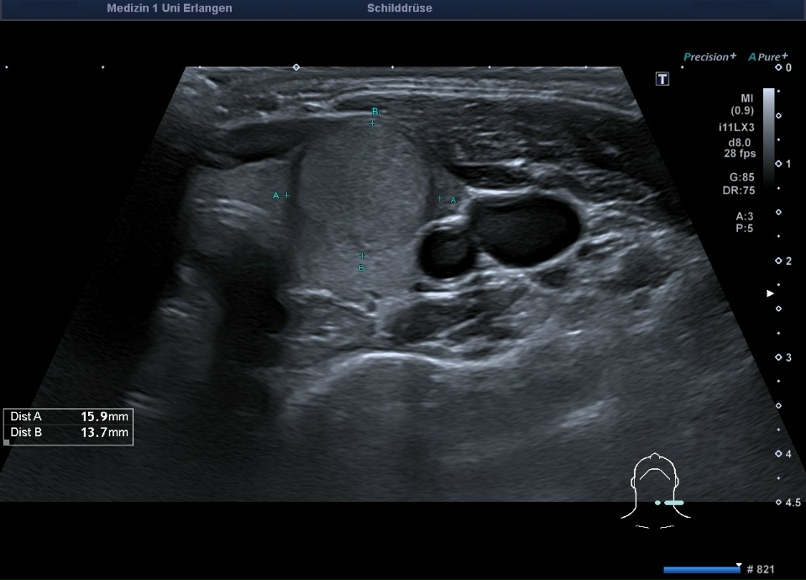

Подавляющее большинство узловых образований щитовидной железы представлены узловым коллоидным зобом небольшого размера, при котором в большинстве случаев показано динамическое наблюдение. Узловые образования в щитовидной железе, которые не пальпируются или не превышают в диаметре 1 см, как правило, не требуют активной диагностики. Пальпируемые или превышающие в диаметре 1 см узловые образования требуют проведение пункционной биопсии щитовидной железы (ТАБ).

В настоящее время для описания узлов рекомендуется использование системы EU-TIRADS. Классификация помогает определить дальнейшую тактику лечения у пациентов с выявленными узловыми изменениями в щитовидной железе.

· EU TIRADS 3 – риск озлокачествления 2-4%, ТАБ показана при узлах более 20 мм

· EU TIRADS 4 – риск озлокачествления 6-17%, ТАБ показана при узлах более 15 мм

· EU TIRADS 5 – риск озлокачествления 26-87%, ТАБ показана при узлах более 10 мм, при узлах менее 10 мм возможно проведение ТАБ или активное наблюдение